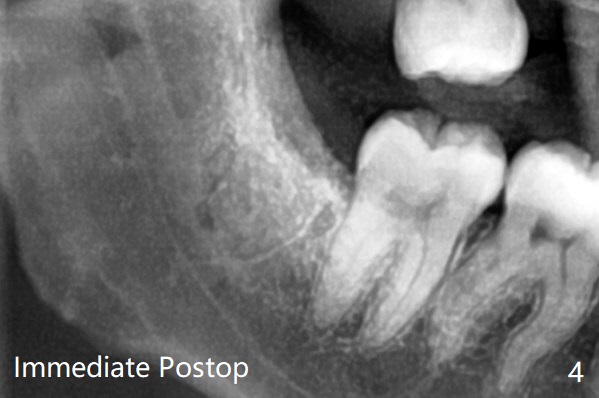

每个牙槽窝放置0.5cc骨水泥(Bone Cement (Bond Apatite from Augma)),覆盖半块胶原塞,4-0铬羊肠线缝合(图四)。